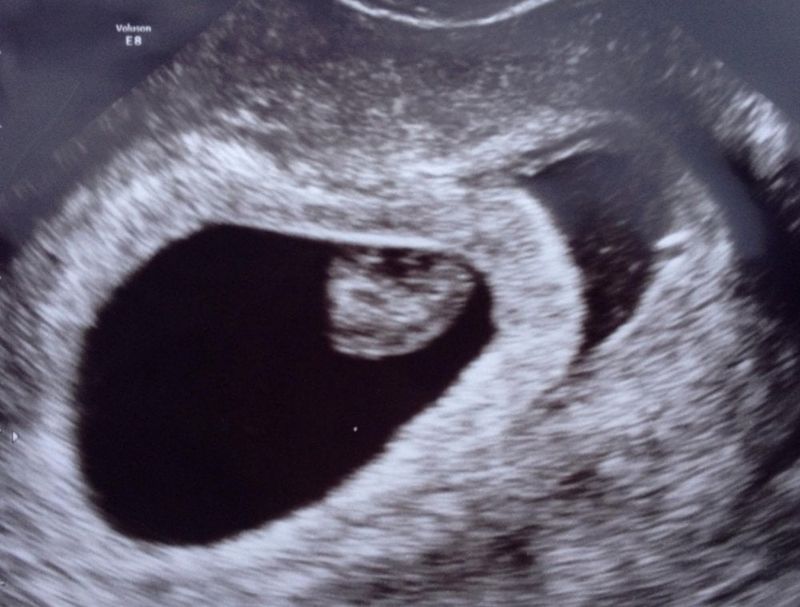

De gynaecoloog wilde dat we even zouden wachten totdat we een bloedonderzoek gehad zouden hebben. Eind oktober werd dit gedaan en pas na de uitslag mochten we het weer proberen. 7 November kwam eraan, Delilah’s geboortedatum. Al een heel jaar hoopte ik opnieuw zwanger te raken, maar op haar eerste verjaardag zat ik zonder Delilah en met een lege buik. Uit het onderzoek kwam niks. Alles was in orde. Maar vanwege de hart- en vaatziektes in mijn familie wilde de gynaecoloog dat ik voor de zekerheid bloedverdunners zou gaan slikken bij een nieuwe zwangerschap. Eind november kregen we weer groen licht en ja hoor, vlak voor Kerst testte ik wéér positief. Vruchtbaar zijn we wel! Nu nog een levend kindje ter wereld brengen (dat we dat konden wisten we al door Vienna, maar het leek wel of we het daarna niet meer konden). Meteen begonnen met de bloedverdunners en dit gaf me een klein beetje meer vertrouwen. Voorzichtig durfde ik hoop te hebben en de eerste echo met zeven weken was goed! Een mooi kloppend hartje en de baby liep zelfs een paar dagen vooruit! Ook de echo’s erna – inclusief de termijnecho – waren goed! Zou dit dan eindelijk ons regenboogkindje worden die mocht blijven? Met 16 weken hadden we een genderecho en we bleken een zoon te verwachten! Ook dit gaf mij vertrouwen, want misschien dat een ander geslacht de sleutel was. Misschien zou het met een jongen wél goed gaan. Veel uitgebreide echo’s, CTG’s en controles volgden en keer op keer bleek ons ‘babyboefje’ – zoals wij hem liefkozend noemden – het supergoed te doen! Totdat ik met 33 weken ongeveer geen beweging voelde..